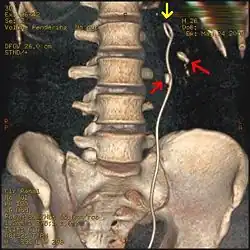

Esami di imaging biomedico

Nelle persone con una storia di calcoli, in coloro di età inferiore ai 50 anni e in quelli che presentano sintomi di calcoli senza alcun segno, non richiedono l'effettuazione di una tomografia computerizzata (TC).[51]

In caso contrario, una scansione TC spirale senza mezzo di contrasto con sezioni da 5 millimetri è la modalità diagnostica di scelta nella valutazione radiografica di una sospetta nefrolitiasi.[6][28][49][52][53] Tutti i calcoli sono rilevabili grazie alla TC, tranne alcuni rarissimi composti da alcuni residui di farmaci nelle urine,[54] come l'indinavir. I calcoli contenenti calcio sono relativamente radiodensi e spesso possono essere rilevati da una radiografia tradizionale dell'addome che includa i reni, gli ureteri e la vescica.[54] Circa il 60% di tutti i calcoli urinari sono radiopachi.[52][55] In generale, i calcoli di fosfato di calcio hanno una maggiore densità, seguiti da quelli di ossalato di calcio e magnesio ammonio fosfato. I calcoli di cistina sono solo debolmente radiodensi, mentre quelli di acido urico sono di solito completamente radiotrasparenti.[56]